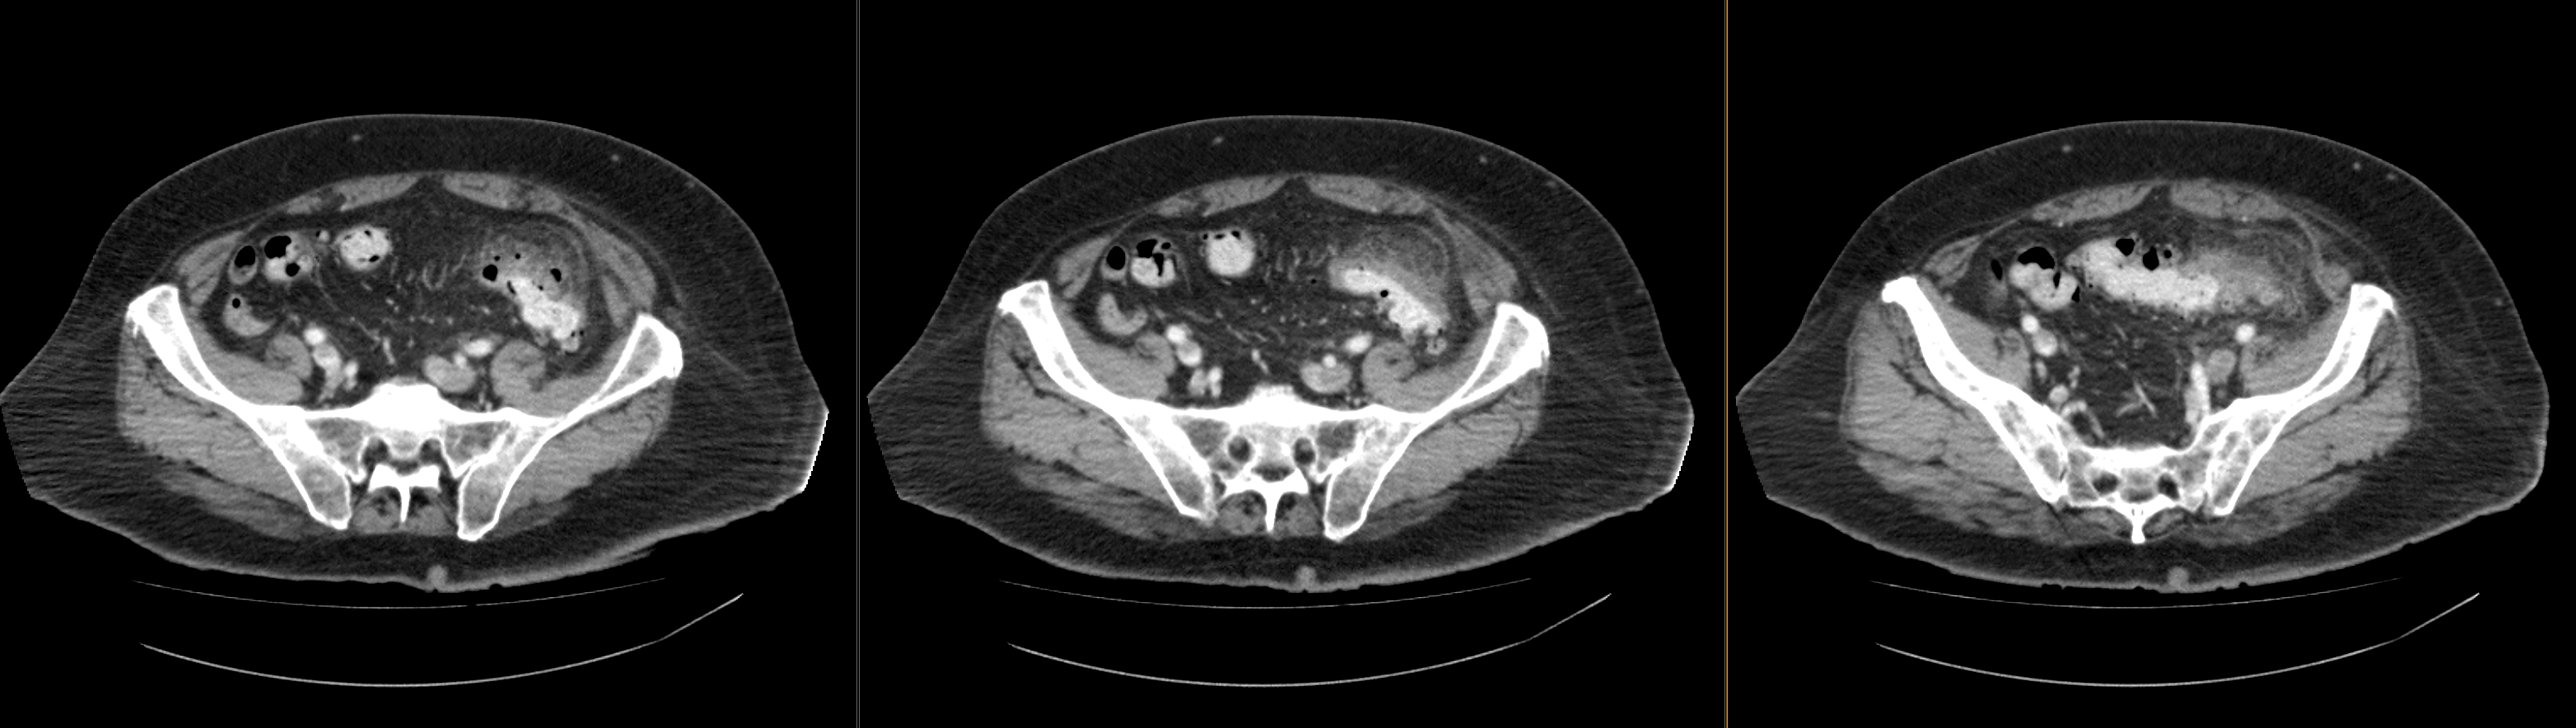

Abdomen/pelvis CT

Selected CT images show inflammation in the RLQ likely from appendicitis.

No, there is inflammation in the left lower quadrant.

View the full study if you'd like to like a look yourself

There is diverticulosis of the sigmoid colon. The thickening with fat stranding around the sigmoid are indicative of inflammation from diverticulitis. There is no fluid collection to suggest abscess.